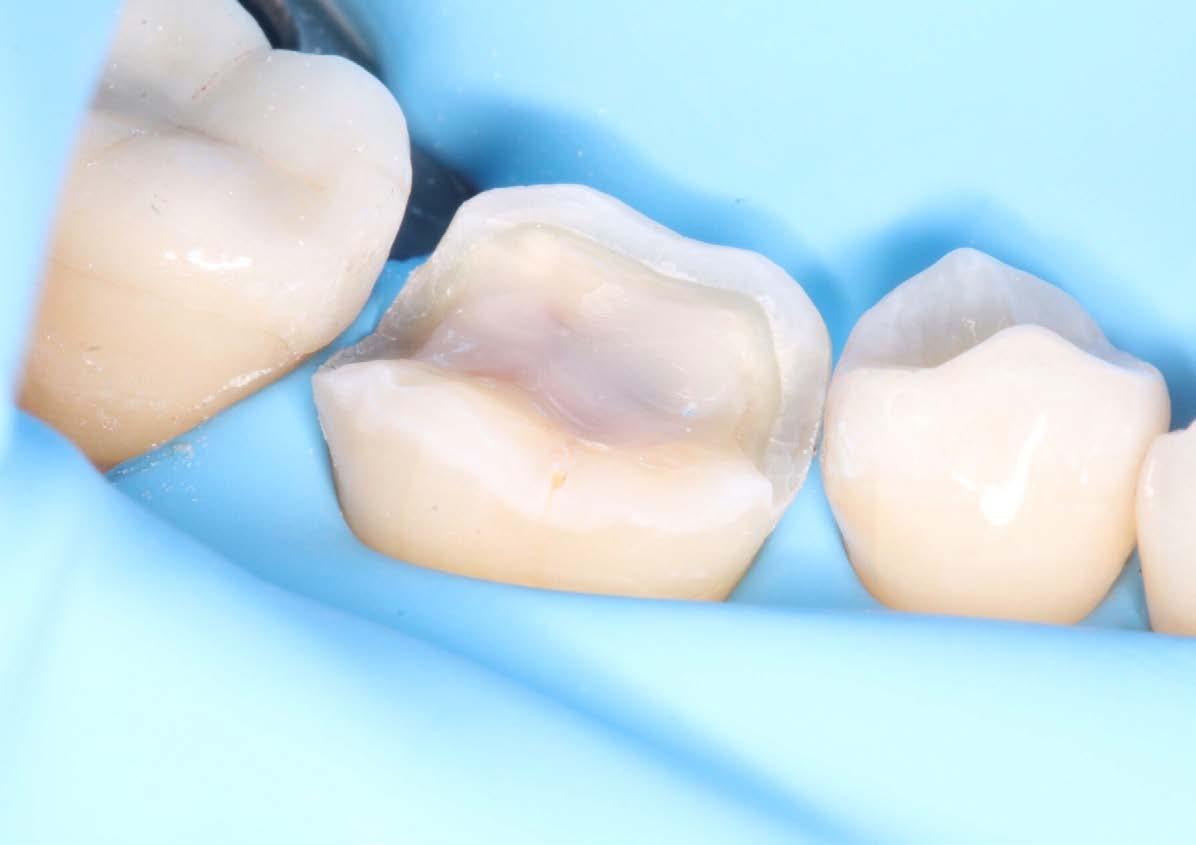

PRESERVING THE TOOTH

7 CPD  Saturday 15 June 8.30am - 5.00pm UWA DENTAL SCHOOL $1287 members

COURSE OUTLINE

Explore the nuances of ceramic onlays and inlays in this one-day course. Learn when to choose each restoration, select materials, master preparation techniques, and ensure successful temporisation and bonding of restorations.

LEARNING OUTCOMES

• Be able to make informed choices for clinical cases

• Differentiate the advantages between onlays and inlays and their respective prescription

• Learn tooth preparation techniques

• Select appropriate materials

• Understand bonding methods

• Communication with patients as to benefits of onlays and inlays